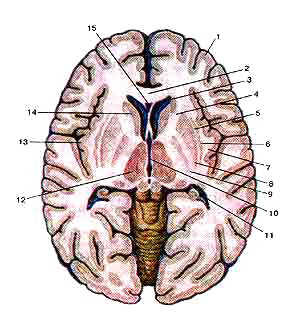

Базальные (подкорковые) узлы (nuclei basales) и внутренняя капсула (capsula interna) на горизонтальном разрезе головного мозга

Вид сверху.

1-кора большого мозга (плащ);

2-колено мозолистого тела;

3-передний рог бокового желудочка;

4-внутренняя капсула;

5-наружная капсула;

6-офада;

7-самая наружная капсула;

8-скорлупа;

9-бледный шар;

10-III желудочек;

11-задний рог бокового желудочка;

12-thalamus (зрительный бугор);

13-корковое вещество (кора) островка;

14-головка хвостатого ядра;

15-полость прозрачной перегородки.